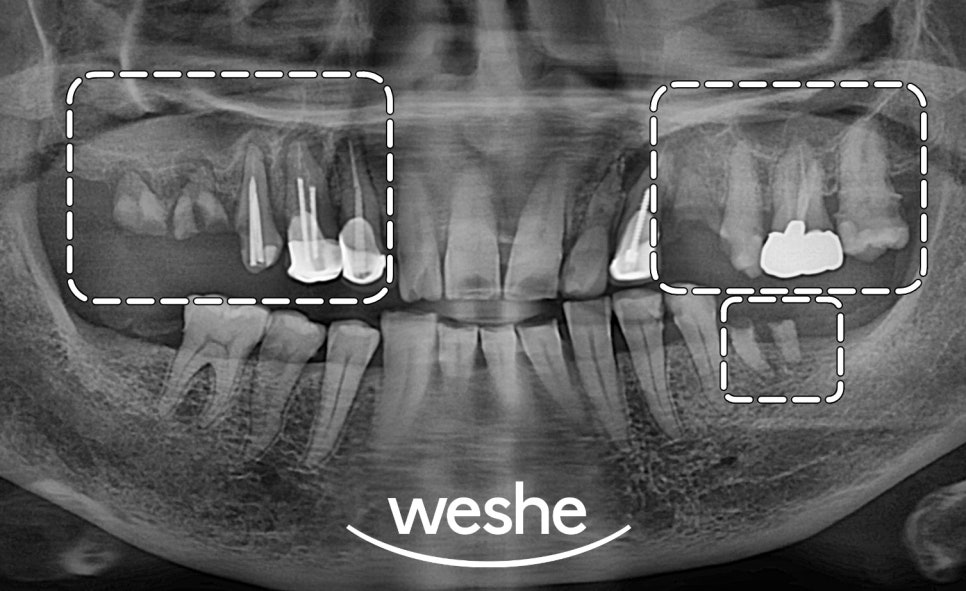

먼저, 엑스레이와 구강 내 모습을 보며

검진을 진행합니다.

예시 사진에서는

치주 질환과 충치로 인해 잇몸뼈가 내려앉거나

치아머리가 사라져 있는 것을

확인할 수 있습니다.

이러한 문제는

자연치의 기능을 하지 못하기에

발치 후 임플란트 를 하는 것이

하나의 방법입니다.

픽스처 식립을 진료 방법으로 선정한다면

3D-CT를 이용하여

구강 내 정보를 분석한 뒤